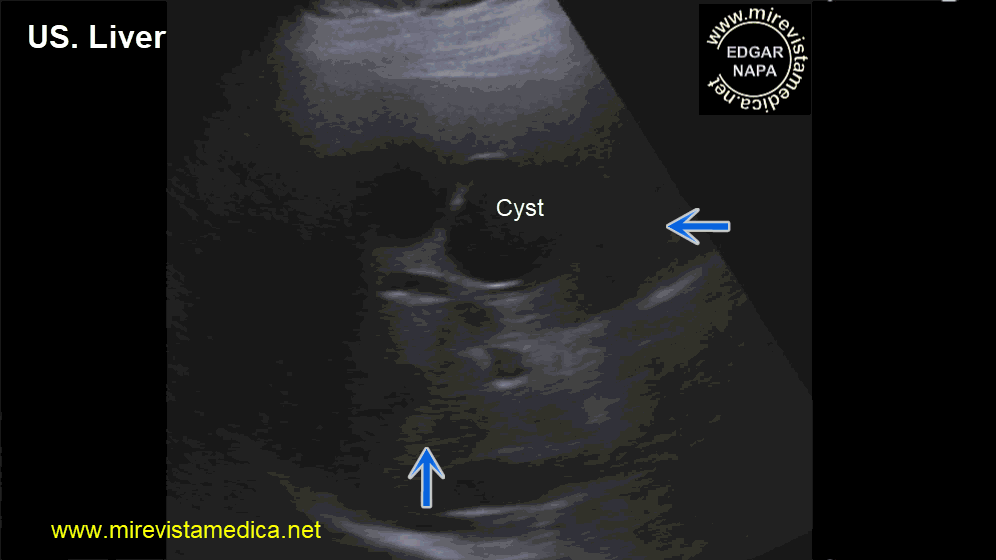

Semiología de los conductos intra y extrahepáticos en ultrasonido